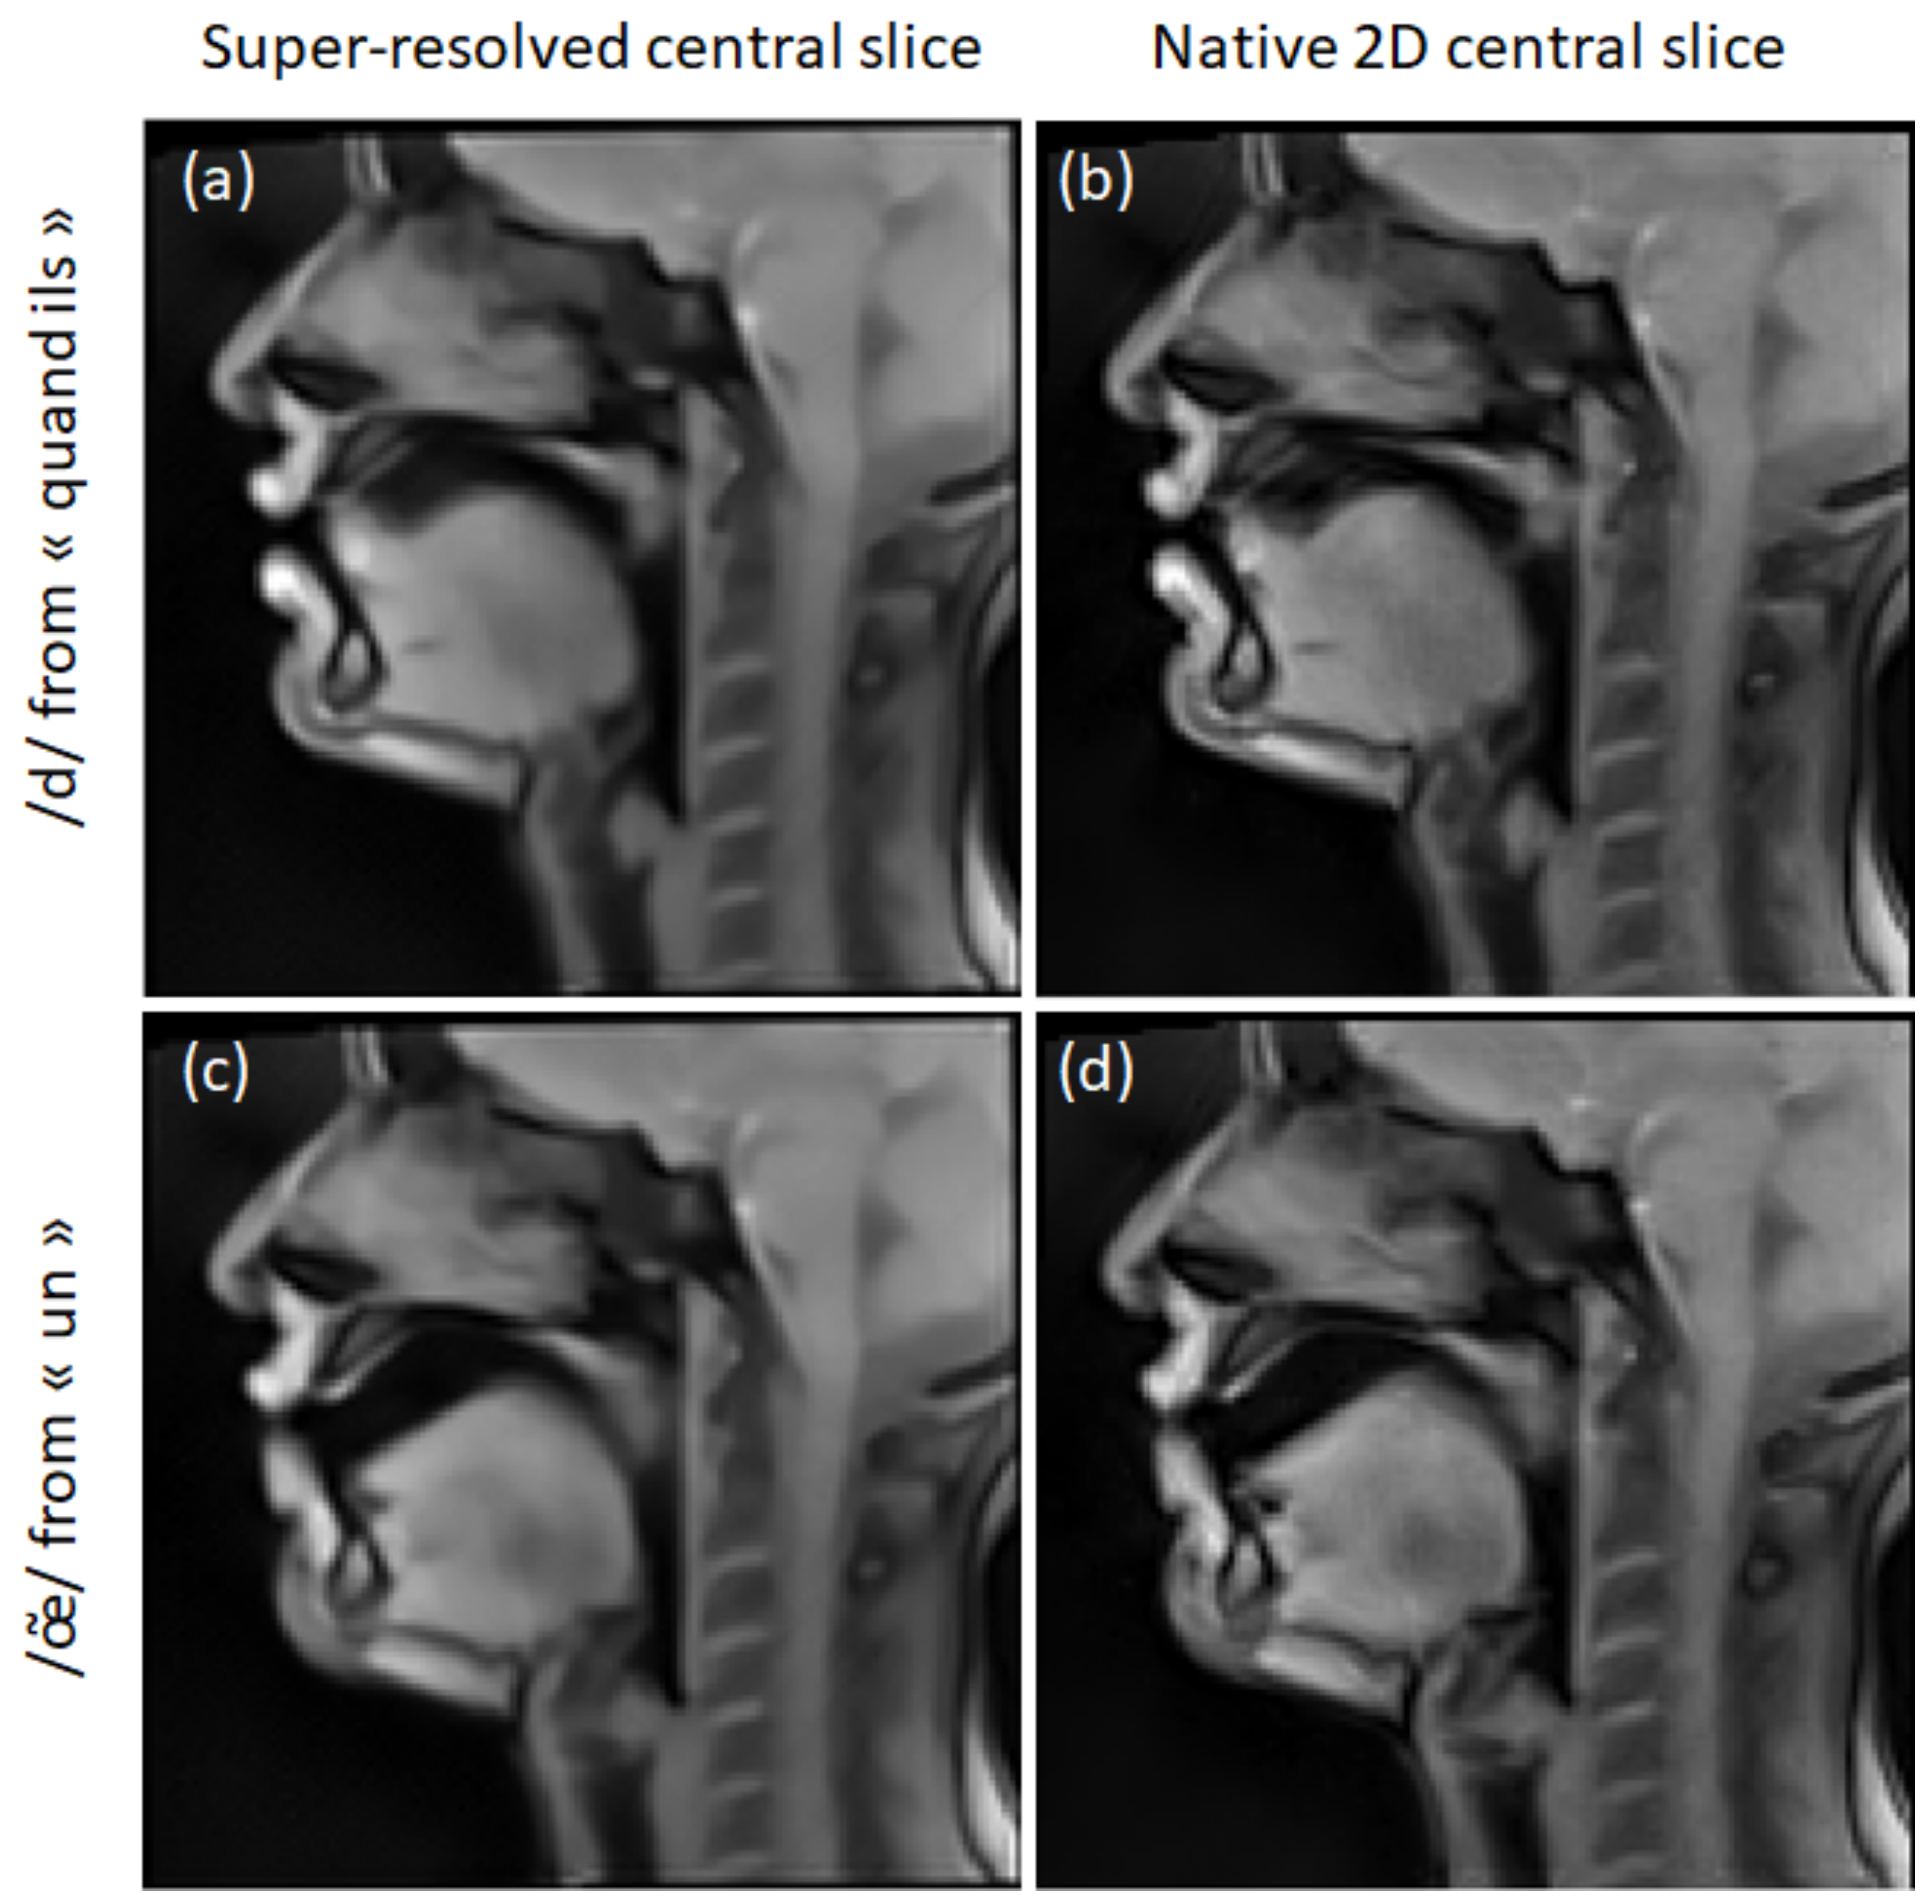

2.4. Super-Resolution

3.2. Super-Resolution